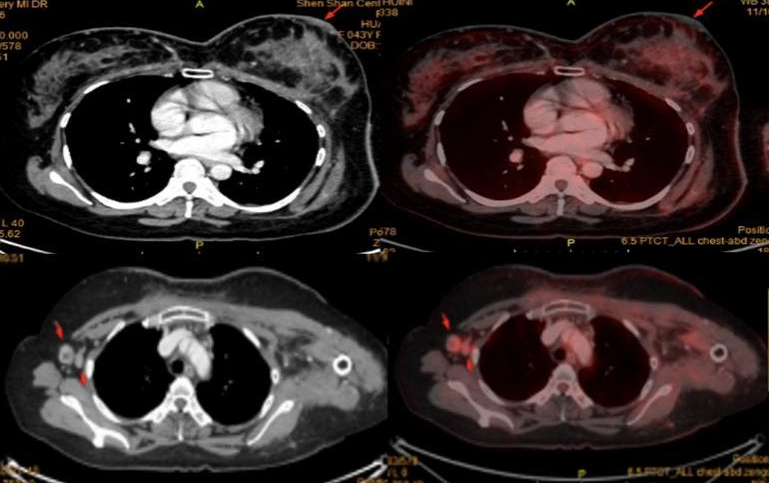

PET-CT:考虑左乳皮皮肤转移伴炎症可能;右侧腋窝淋巴结转移。余未见明显异常。

6程后复查乳腺MR、胸部+上腹部CT、乳腺彩超,提示:左乳病灶范围较前明显缩小,右腋窝肿大淋巴结消失。